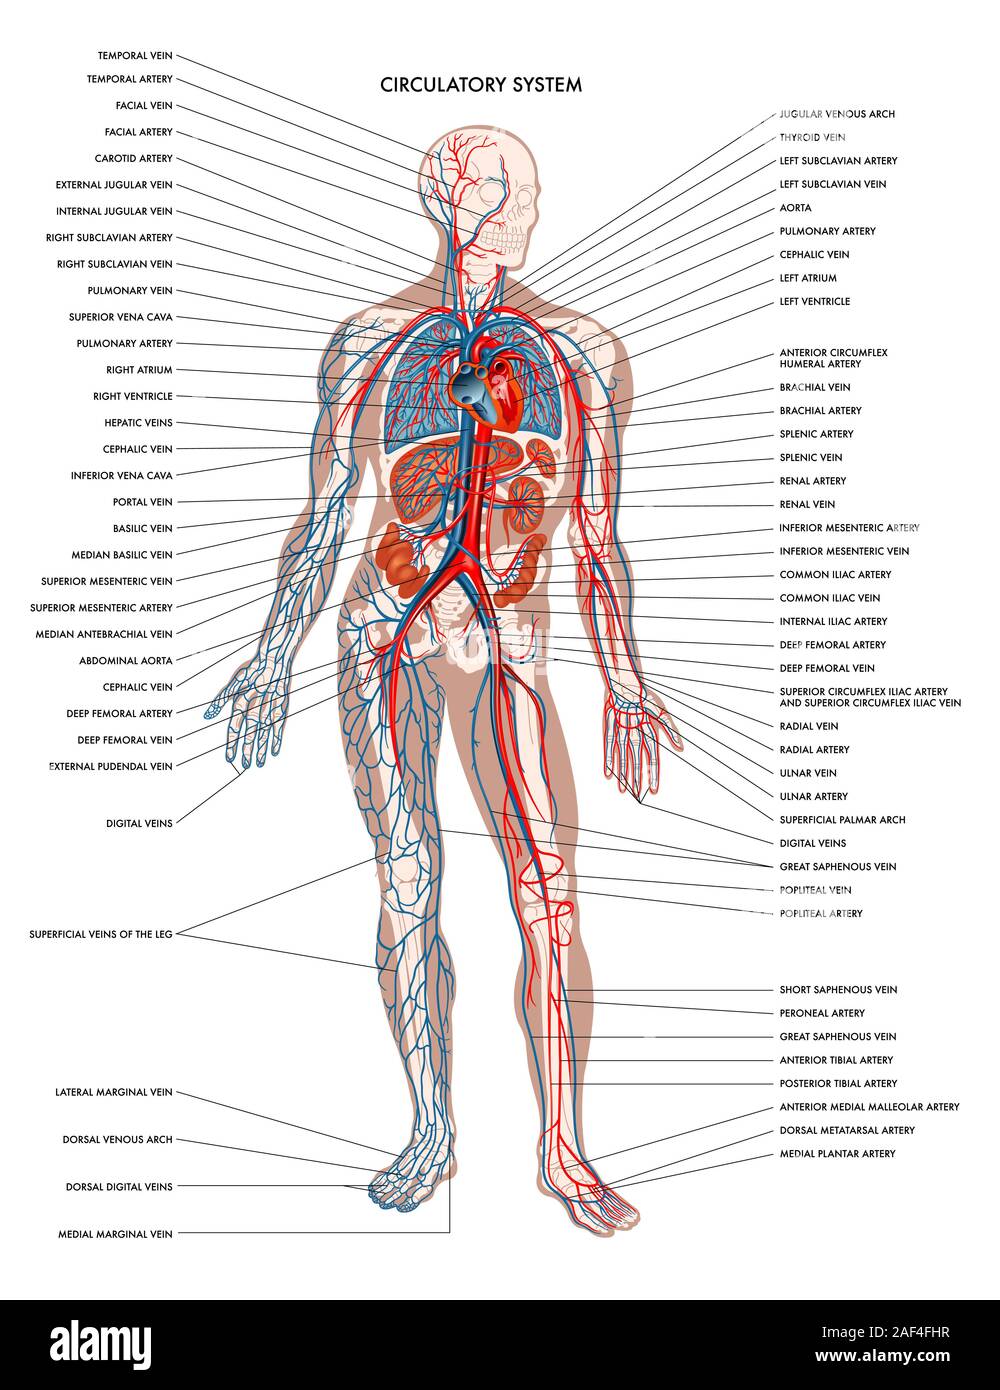

Labelled diagram showing the details of the human body circulatory system. Stock Photohttps://www.alamy.com/image-license-details/?v=1https://www.alamy.com/labelled-diagram-showing-the-details-of-the-human-body-circulatory-system-image336316899.html

Labelled diagram showing the details of the human body circulatory system. Stock Photohttps://www.alamy.com/image-license-details/?v=1https://www.alamy.com/labelled-diagram-showing-the-details-of-the-human-body-circulatory-system-image336316899.htmlRF2AF4FHR–Labelled diagram showing the details of the human body circulatory system.